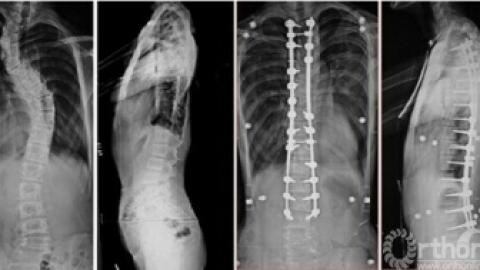

马凡氏综合征,绝对好病例! [病例帖]

马凡氏综合征

马凡氏综合症。(7)家族或遗传史主要标准:父母、子女或兄弟姊妹之一符合该诊断标准;FBNI基因中存在已知的导致马凡综合征的突变;存在已知的与其家族中马凡综合征患者相同的FBNI基因单倍型。马凡综合征的诊断前提对特定病例:如果无家族或遗传史者,至少需有两个不同系统的不要标准以及三分之一的器官受累;如果检出一个已知马凡综合征的基因突变,一个系统中有一项主要标准和第二项系统受累即可诊断。